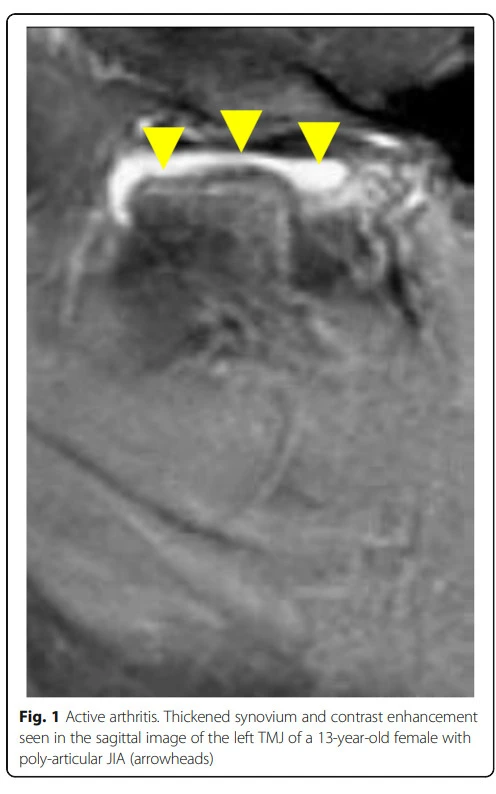

그림출처: Stoll, Matthew L., et al. "Temporomandibular joint arthritis in juvenile idiopathic arthritis, now what?." Pediatric Rheumatology 16.1 (2018): 32.

문제는 바로 위와 같이 뼈 자체가 녹아버린 것입니다. 저렇게 erosion이 생겨버리면 두 뼈의 위치관계가 달라질 수밖에 없는데 자연스럽게 반복되는 저작운동으로 인하여 부식된 부위의 공간만큼 하악골의 상방이동이 일어날 수밖에 없게 됩니다.

저 지점이 바로 안면비대칭의 첫 시작입니다. 턱관절 증상이 발생하였을 때 안면비대칭을 염두에 두고 치료를 시작하는데, 그 이유가 바로 턱관절 염증이 심하면 심할수록 저렇게 조직손상이 이루어질 수가 있기 때문입니다.